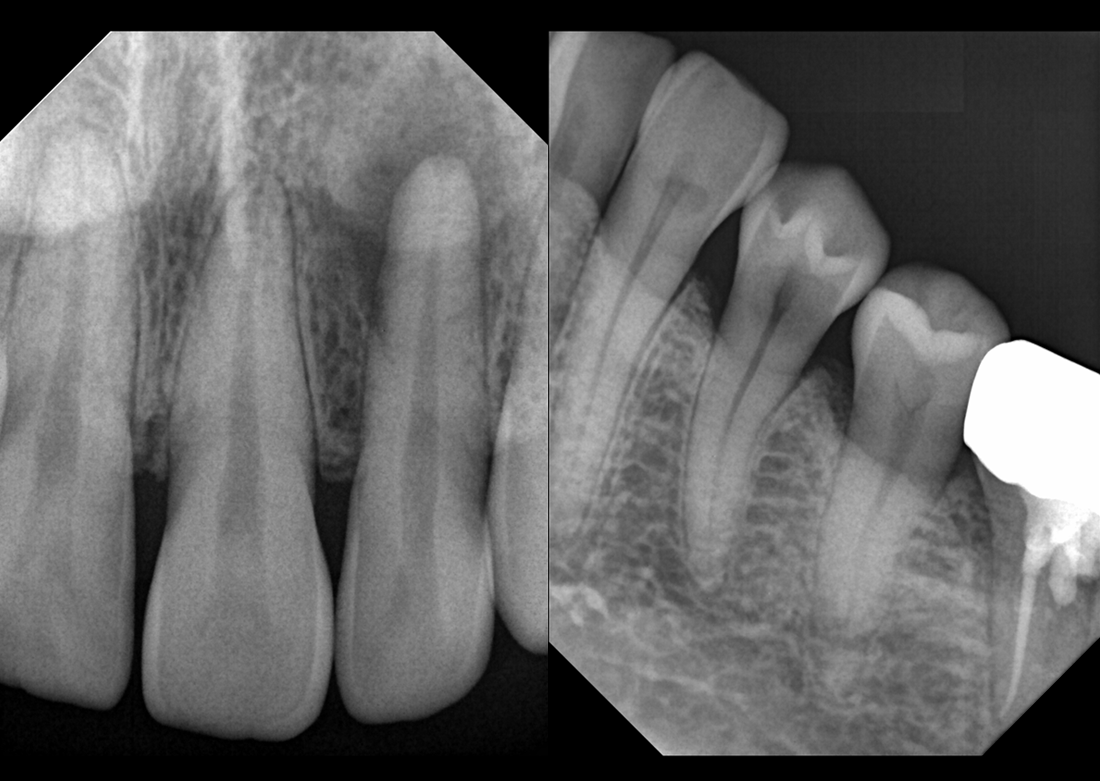

KLİNİK FOTOĞRAFLAR

Firmanın uzun yıllara dayanan dental görüntüleme tecrübesi ile son teknoloji sensor reseptörleri kullanılarak üretilmiştir ve görüntü kalitesi mükemmel düzeydedir.